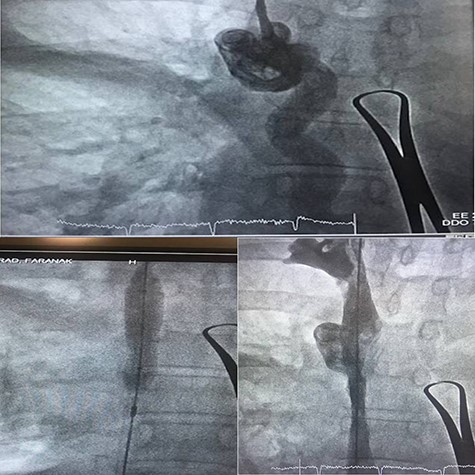

Magnetic resonance imaging was scheduled to evaluate brain metastasis. The venogram showed occlusion in the SVC. As the patient’s symptoms presented in <1 month, we passed a thrombolytic catheter through the port line, and the port was removed. Thrombolytic agent and heparin infusion were prescribed for 48 h. Repeated venogram revealed remained occlusion in SVC, so balloon venoplasty was done a day later (Fig. 2). The procedure was uncomplicated. The patient’s symptoms were remarkably improved at the time of discharge.

SVC syndrome is diagnosed clinically with an in depth history and physical exam. However, imaging is required for a definitive diagnosis. Contrast venography can confirm the diagnosis of SVC syndrome and also for direct treatment and monitor the progression of therapy [4]. Computed tomography angiography or magnetic resonance angiography are superb modalities for diagnosis and may quickly be used. Our patient had typical history and physical exam, so we used ultrasound initially because it is quick, inexpensive and venography was done to verify the diagnosis and treating SVC thrombosis with endovascular balloon venoplasty. She had bilateral mastitis, she was referred to us later. As we weren’t certain about the accurate time of thrombosis, thrombolytic therapy was conducted first, but stenosis didn’t differ significantly in repeated venography. Hence, we decided to perform balloon venoplasty.